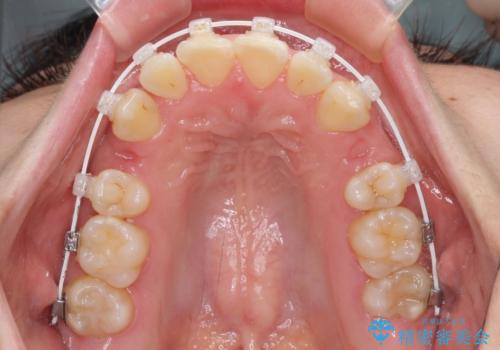

- 矯正装置

- 審美装置

当初予定は2年半程度と伝えていましたが、2年にも満たない期間で治療を終えることができました。